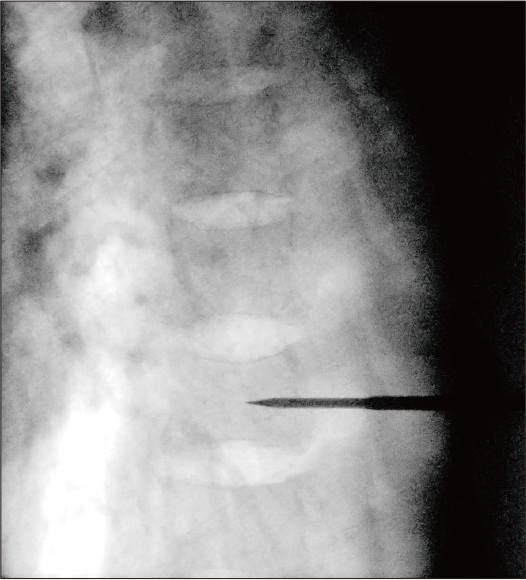

Allgemeine Verarbeitung

Dosis: 8,4 mA

Nach Anwendung der dynamischen Verarbeitung